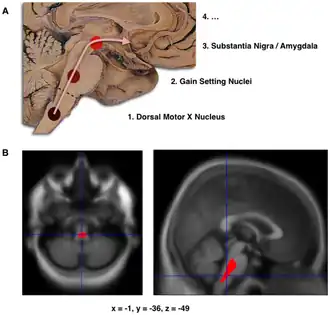

B. Localization of the area of significant brain volume reduction in initial PD compared with a group of participants without the disease in a neuroimaging study which concluded that brain stem damage may be the first identifiable stage of PD neuropathology.[1]

The staging in Parkinson's disease was described by Heiko Braak in 2003.[4] Braak and colleagues state that Parkinson's disease begins when a foreign agent enters the body via the nose or gastrointestinal system and travels into the central nervous system (CNS). The presence of Lewy bodies in the enteric and peripheral nervous systems supports their claim. This Lewy body pathology selectively travels through the CNS, targeting thin and largely unmyelinated neurons. Braak et al., therefore, developed a staging system that characterizes disease progression. This system is divided into six different stages, with each stage being attributed to abnormal pathology in particular neurological structures. In terms of symptomatology, the type and severity of symptoms is correlated to progression through the Braak stages.[5] Early stages are characterized by non-motor symptoms, such as a lessened sense of smell or constipation. Motor symptoms are often displayed around the mid-stage state, and cognitive symptoms arise as later Braak stages are reached.[6] Braak and colleagues further state that the disease begins in the enteric nervous system and gains entry to the CNS through the vagus nerve.[7]

The disease begins in structures of the lower brainstem and the olfactory system. In particular, the dorsal motor nucleus of the vagus nerve in the medulla oblongata and anterior olfactory nucleus are affected.[6] Lewy neurites, thread-like alpha-synuclein aggregates, are more prevalent than globular Lewy bodies in this stage.[4]